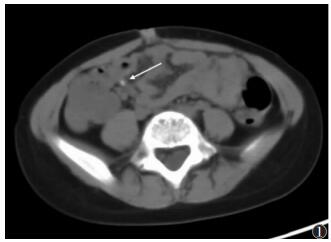

① 9例急性单纯性阑尾炎,MSCT示阑尾管腔均增宽,外径6~9 mm,管腔内多伴少许积液,管壁增厚不明显,管壁边缘及周围脂肪间隙密度模糊,表现为细网线状略高密度影;7例粪石均可显示(图 1),MSCT表现为直径为25 mm的点状或小类圆形高密度影,多位于阑尾根部;伴盆腔积液2例,回盲部周围淋巴结肿大1例。②19例急性化脓性阑尾炎,MSCT示阑尾管腔均增宽,外径8~14 mm;12例伴高密度粪石,当圆形高密度粪石嵌顿在阑尾根部,远端管腔因阻塞常增宽明显;阑尾管壁肿胀,厚度>3 mm,边缘模糊不清,管腔内多伴积液及气泡,6例管腔周围伴脓肿形成,CT表现为高于水样密度影,可伴气泡;4例阑尾脓肿伴穿孔MSCT示2例阑尾局部管壁连续性中断(图 2);5例肠淤张,表现为腹盆部小肠呈不同程度扩张,肠管拥挤,管腔内积气积液;伴盆腔积液14例,肠系膜周围淋巴结肿大2例。③16例急性坏疽性阑尾炎,MSCT示阑尾管腔不同程度扩张,外径7~18 mm,管壁明显增厚(图 3);4例局部管壁连续性中断,管腔周围可伴脓肿及气泡;14例管腔内伴圆形高密度粪石,管腔内积气、积液;9例管壁周围脂肪密度可见条状、片状增高,邻近回肠末端及盲肠管壁增厚;6例肠淤张;伴腹盆腔积液10例,肠系膜淋巴结肿大4例。

| 图 1 男,6岁,急性单纯性阑尾炎,阑尾外径6 mm,阑尾根部管腔内见一小结石(长箭),管壁略增厚 |